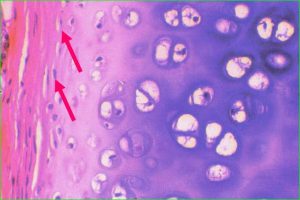

![]() 톈진(天津)대학 화공학원 장레이(张雷)/양징(杨静) 연구팀은 새로운 세포 초저온 보존 기술을 성공적으로 개발함으로써 최초로 저비용, 무독성, 무부작용의 인간 연골 세포 초저온 보존을 구현했다. 세포 치료 분야의 이 획기적인 성과는 혈액질환과 암 환자에게 좋은 소식을 가져다주었다. 해당 성과는 "Biomacromolecules"에 게제되었다. 세포치료는 세포를 체외 배양한 후 환자 체내에 이식하여 인체의 손상된 조직 또는 세포를 복구하거나 대체하여 치유하는 것을 말한다. 세포를 초저온 냉동 보존하여 미래에 "깨우"거나 치료하는데 사용하는 것은 인류 의학 발전사에서 가장 상상력이 풍부한 "후회약"으로 불린다. 세포가 저온 냉동시 손상 받지 않도록 하기 위해 기존에는 주로 유기 보호제인 다이메틸설폭사이드(DMSO)를 첨가했다. 해당 보호제는 자체적 독성이 있기에 세포가 냉동에서 복구된 후 반드시 복잡한 독성 세척 절차를 거쳐야만 배양 확장 또는 환자의 체내에 주입할 수 있다. 독성 세척 후에도 소생된 세포는 환자의 메스꺼움과 구토, 기관지경련, 신부전 및 심정지와 같은 많은 부작용을 일으킬 수 있다. 또한, 중국의 임상응용 냉동보존 보호제는 줄곧 수입품에 의존하여 가격도 아주 비싸다. 연구팀은 창조적으로 천연 양성 이온 베타인을 세포 냉동보존 보호제로 사용하여 인체 연골 세포의 초저온 보존에 성공했으며 세포 소생의 생존율은 90%이상에 달했다. 실험 결과, 해당 보호제는 연골 세포의 활성과 기능에 뚜렷한 손상이 없고 세포 소생 후, 보호제 용출의 복잡한 과정이 필요 없이 직접 임상 치료에 사용될 것으로 예상된다. 해당 연구 성과는 중국 특허를 받았고 국제 PCT 특허를 출원했다. 또한, 다양한 종류의 인체 세포에도 실험 중이다. 새로 개발한 세포 초저온 보호제는 세포에 완전 무독무해하고 기존의 수입제품을 대체할 수 있으며 과학 연구와 임상 비용을 대폭 절감시킬 수 있다. 정보출처 : http://digitalpaper.stdaily.com/http_www.kjrb.com/kjrb/html/2019-10/22/content_433131.htm?div=-1 |